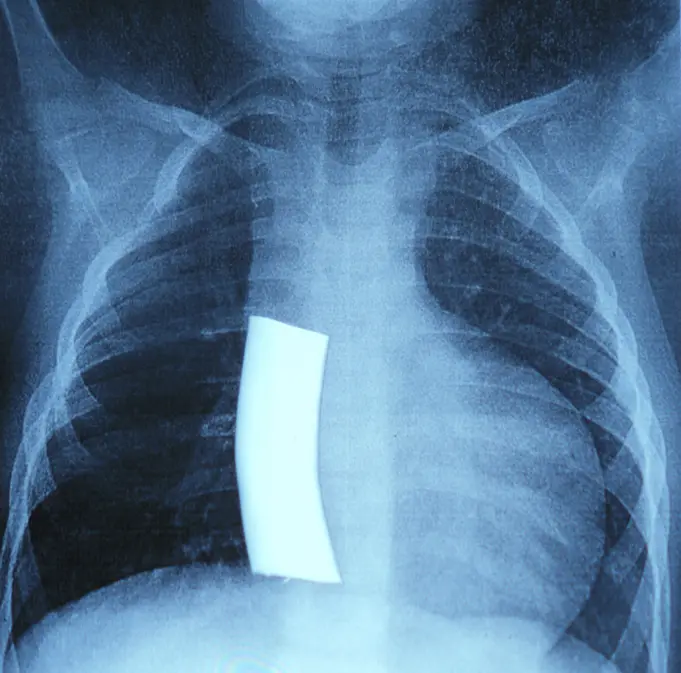

X-ray of infant with hypoplastic left heart syndrome

The initial procedure created a shunt that sent blood from the body through the lungs, bypassing the heart. This allowed a single ventricle to send blood to the body and lungs simultaneously.

The Fontan saved thousands of lives. But it became more valuable when paired with the Glenn and Norwood procedures. These two procedures “set the stage” for the Fontan. This staged heart reconstruction is necessary for children with hypoplastic left heart syndrome (HLHS).

Largely considered one of the most critical CHDs, more than 1,000 babies are born in the United States with HLHS every year. Without surgery, most babies die within two weeks of being born.